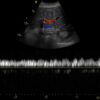

GE C1-6-D Abdominal Convex Refurbished

GE Convex C1-6-D Abdominal

Intended use

Abdominal and Women’s Health

Frequency Range

6 – 1 MHz

System compatibility

LOGIQ, VIVID

GE C1-6-D Abdominal Convex

Frequency Range: 6 – 1 MHz

GE C1-6-D Abdominal Convex for Abdominal and Women’s Health

Compatible with GE Systems